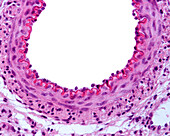

13742427 - Elastic artery, light micrograph